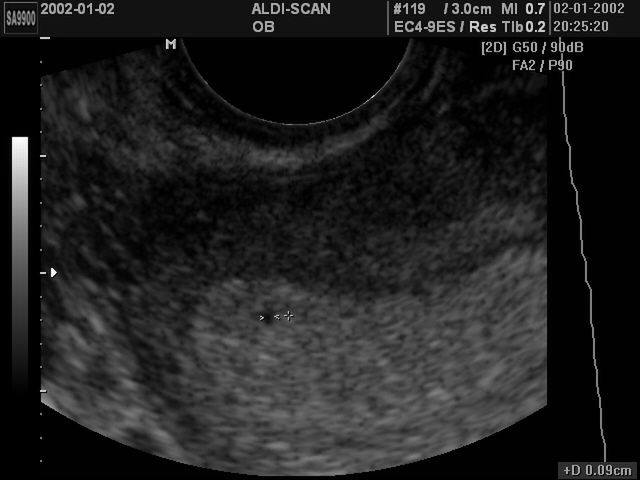

Rozwój płodu jest etapem następującym po zapłodnieniu, czyli połączeniu jądra plemnika z jądrem komórki jajowej. Rozwój prenatalny można podzielić na cztery etapy. Pierwszy etap rozwoju płodu to okres przedimplantacyjny, a kolejne to tworzenie listków zarodkowych, okres organogenezy i okres płodowy. Okresy rozwoju płodu przebiegają bez zakłóceń, gdy ciężarna kobieta dba o siebie i dziecko. Prawidłowy rozwój płodu monitoruje się poprzez regularne wykonywanie badań w ciąży.

Zanim dziecko przyjdzie na świat, musi spędzić dziewięć miesięcy w brzuchu matki. Przez te dziewięć miesięcy będzie się rozwijało i zmieniało, aż pewnego dnia będzie gotowe do wyjścia na świat.